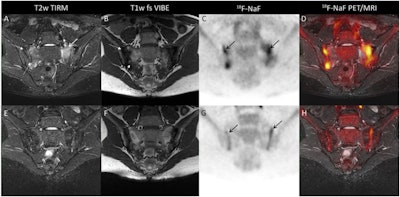

- The team observed an increasing trend in bone and joint publications (12 of 65) over the course of the study's time frame.